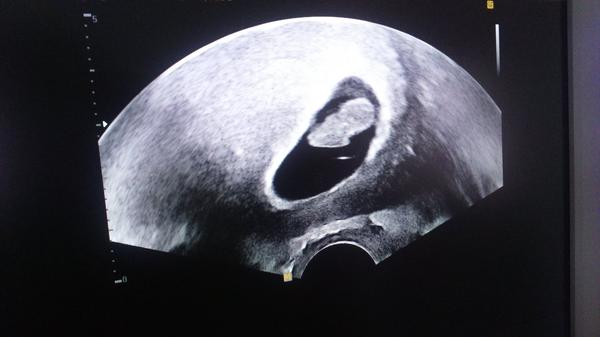

Konečne som sa dočkala prvej prehliadky 🙂 srdiečko bije, všetko ako má byť 😉 lekárka mi tvrdila že som 8+1. No nadšení sme 😉